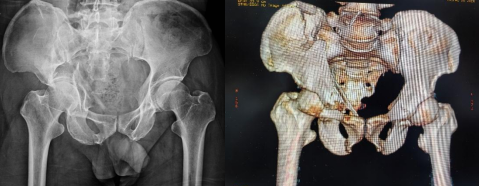

術后DR與CT顯示骨折復位固定好,關節面平整

手術期間,該院骨科團隊按照術前規劃,精準入路完成了良好的復位和固定,整個手術用時短,創傷小,出血量顯著減少,患者疼痛輕。術后復查顯示,關節面平整,頭臼關系匹配良好,且患者恢復迅速。